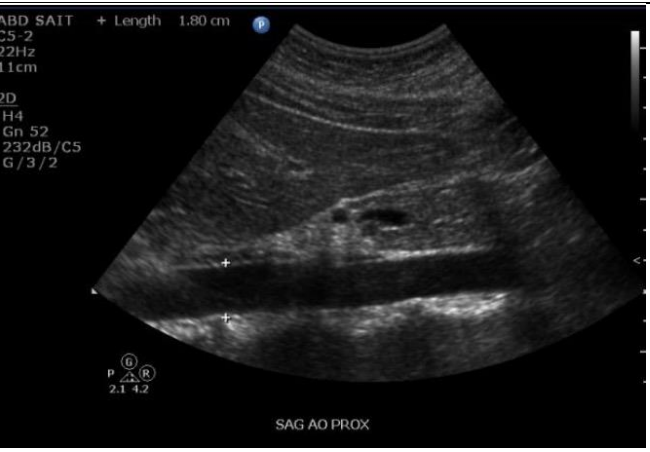

4

Q

Label the Red and blue arrows

A

Red: Body of pancreas

Blue: GE junction